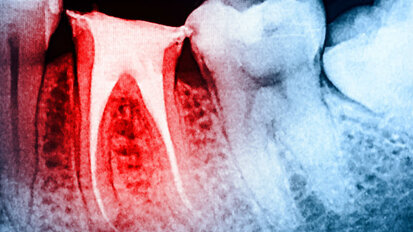

X Congresso Internazionale AIO, a Chia l’indagine in endodonzia si colora di “giallo”

Rigenerazione del complesso polpa-dentina, gestione del dolore, procedimenti velocizzabili, soluzioni ricostruttive: è rappresentato tutto il percorso di ...

10° Congresso Internazionale AIO: scegli il tuo percorso

Percorso giallo endodonzia, percorso rosso parodontologia e implantologia, percorso verde protesica e restaurativa, percorso azzurro pedodonzia ed ...